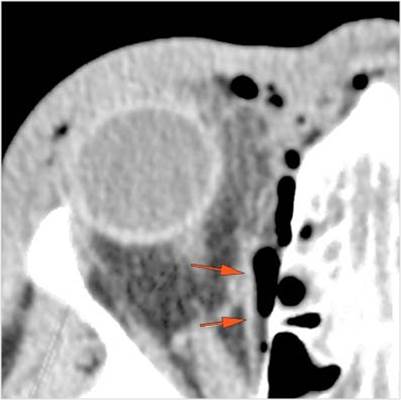

There is evident general optic sheath swelling or swelling at the junction of the globe and sheath to suggest an optic sheath hematoma. [Yes/No]

There is evident subretinal, subchoroidal or intravitreous hemorrhage. [Yes/No]